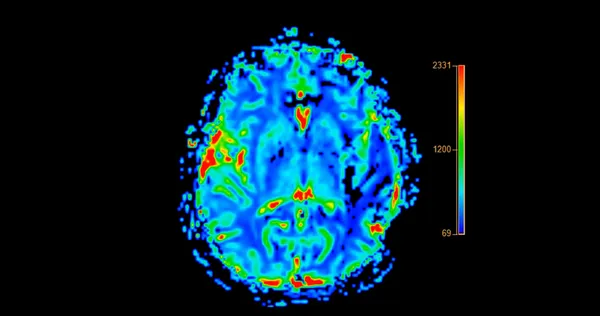

Aynı alzaymır tanısını alan iki kişide bile hastalığın farklı seyredebileceğini vurgulayan Doç. Dr. Uysal, "Bazı hastalarda unutkanlık ön plandayken, bazılarında kelime bulma güçlüğüyle başlayan dil problemleri görülebilir. Erken dönemde öfke, içe kapanma veya şüphecilik gibi davranış değişiklikleri de ortaya çıkabilir. Bunun temel nedeni hastalığın beynin hangi bölgelerini ve hangi sırayla etkilediğidir" diye konuştu.

"Beynin ön bölgeleri etkilendiğinde kişilik ve davranış değişiklikleri, yan bölgeler etkilendiğinde dil bozuklukları, derin yapılar etkilendiğinde ise halüsinasyonlar görülebilir. Hasta yakınlarının 'Eskiden böyle biri değildi' tepkisi anlaşılırdır ancak hastalık kişinin karakterini değil, beynini değiştirir. Hastalıkların birbirleriyle kıyaslanması doğru değildir."